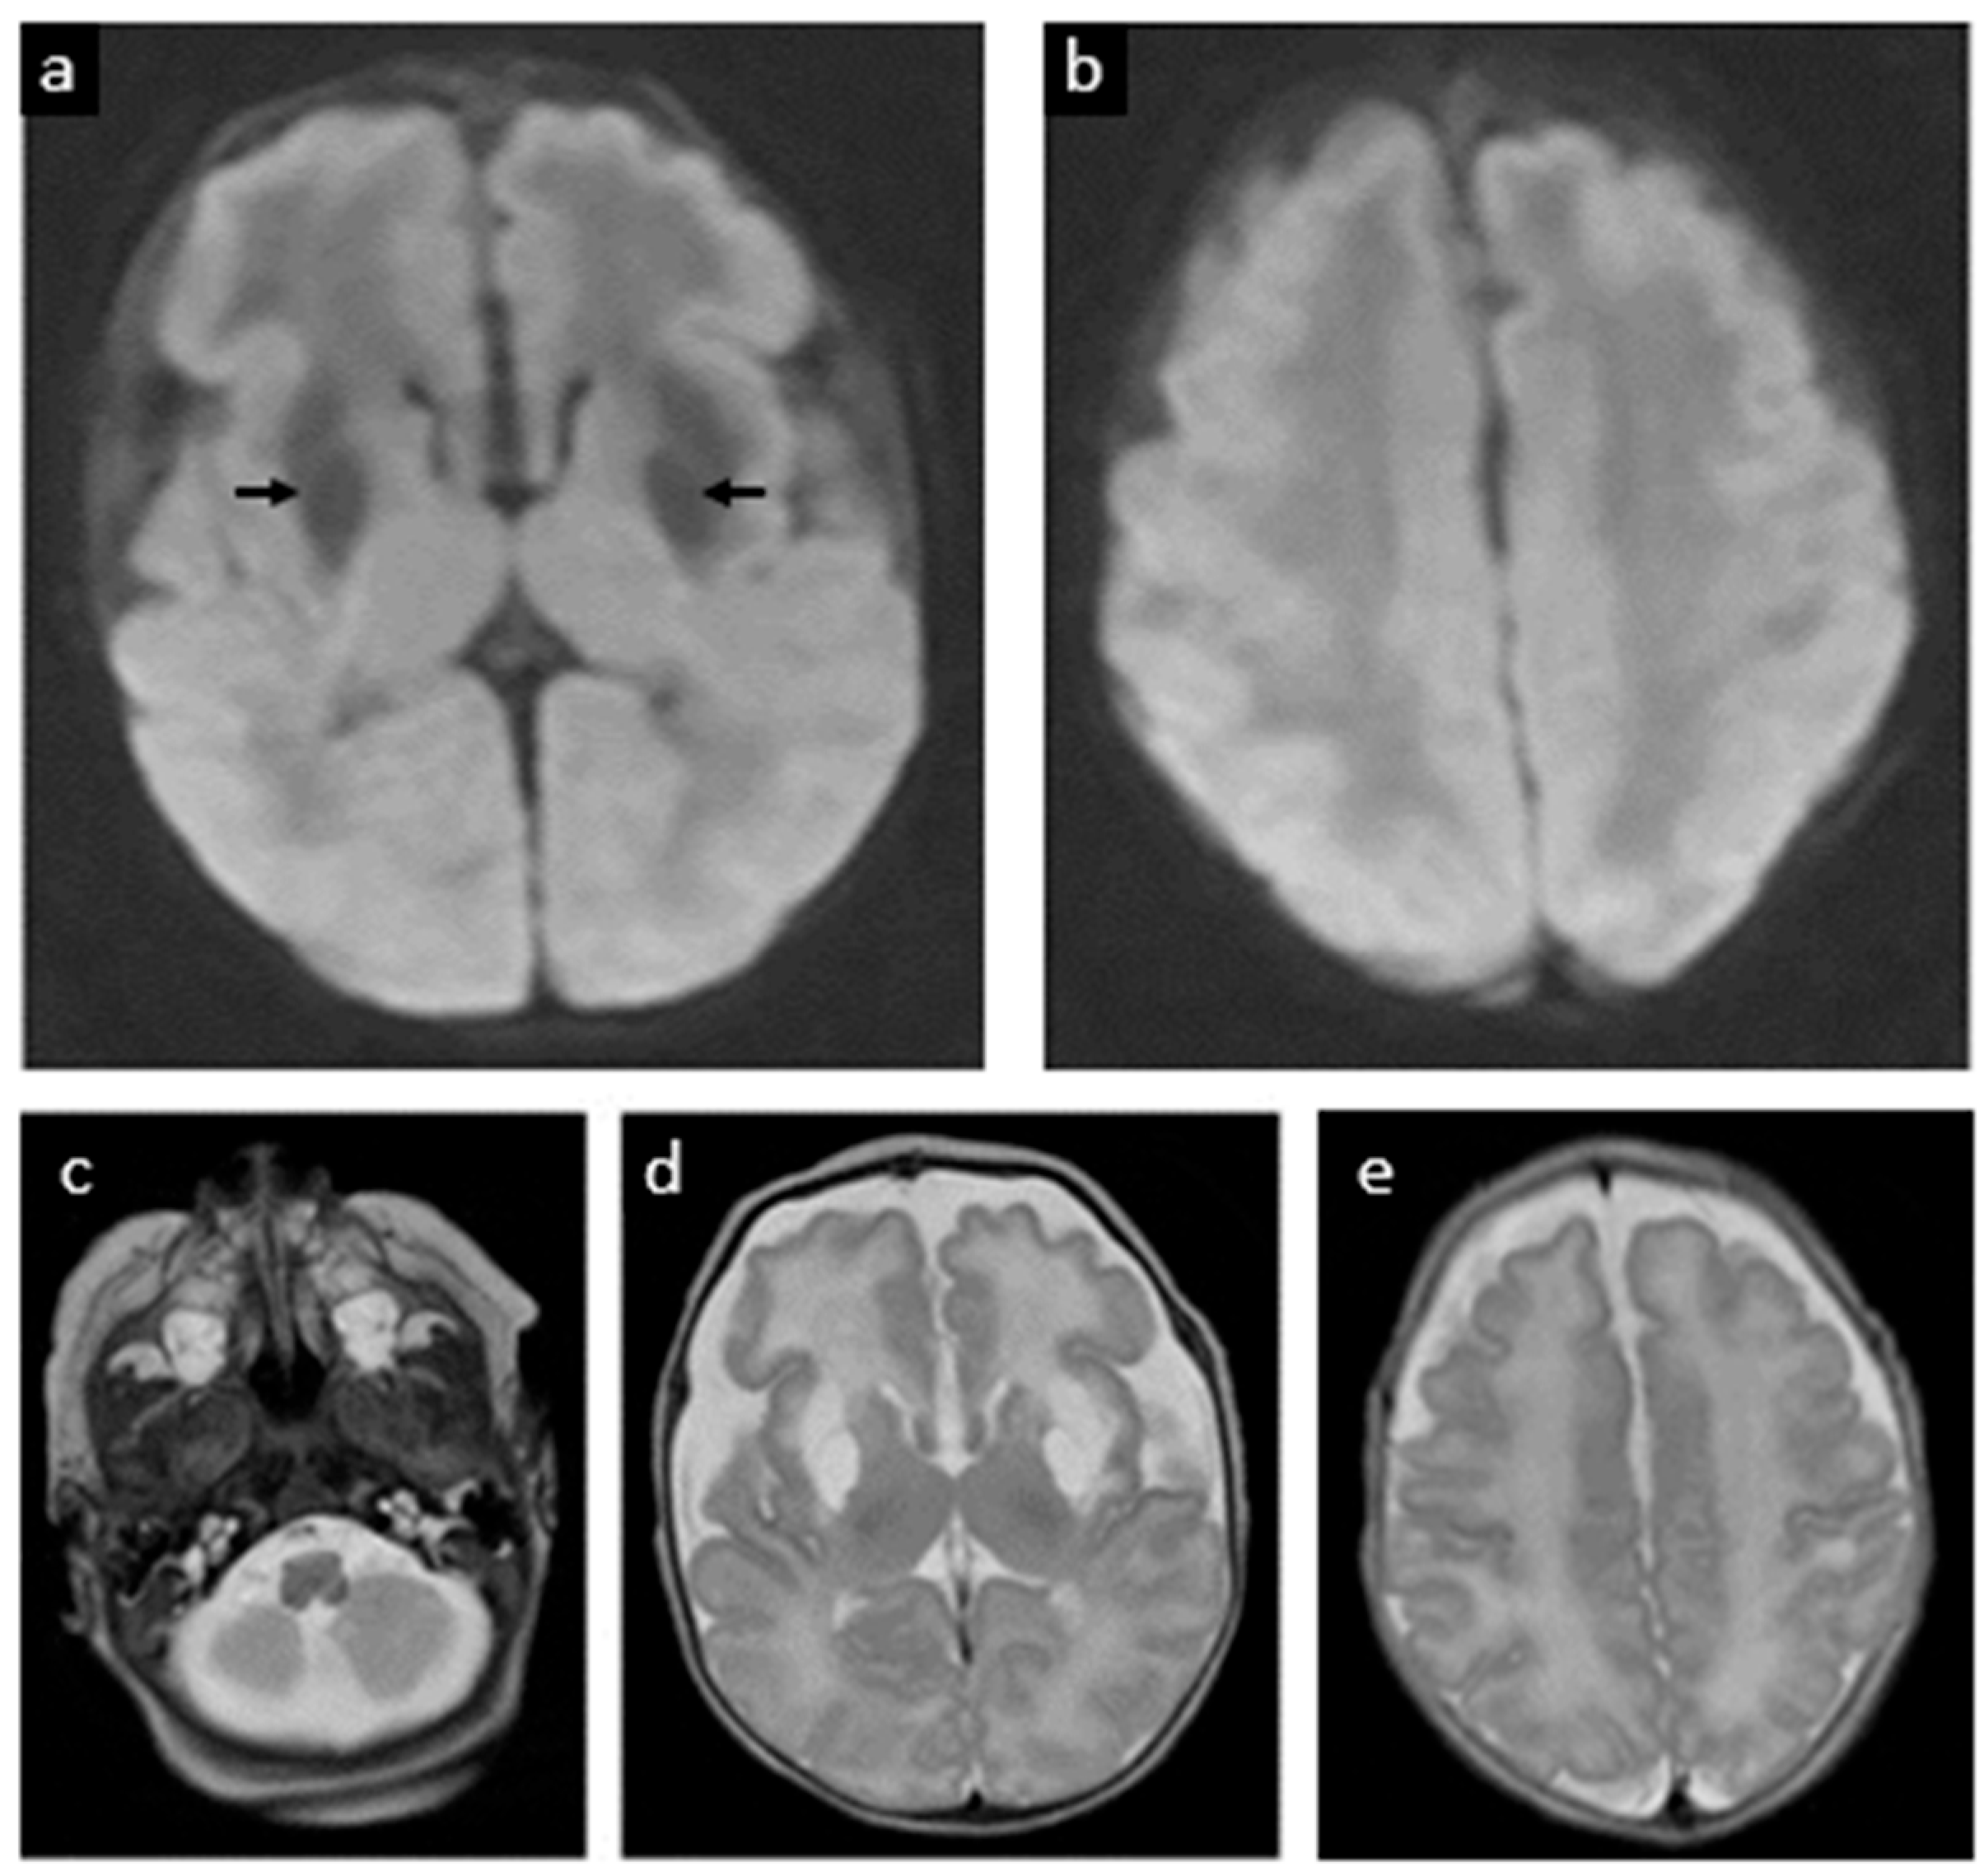

| 15 | Schwahn et al., 2024 [19] | No | None reported | Day 4 | 39 w 2 d | Early brain MRI at 5 days revealed transient edema and signal changes in globi pallidi, resolving by week 6. Long-term neurodevelopment showed mild muscular hypotonia and delayed cognitive milestones |

| 16 | Etchegaray et al., 2025 (this case) | Yes (16 w via amniocentesis) | Fetal MRI normal at 22 w; mega cisterna magna at 28 w | Day 0 (within 10 min of birth) | 32 w 6 d | Neonatal seizures (resolved by 60 h); discharged D37. Developed dystonic quadriplegic CP by 6 mo (cognition relatively spared); remains seizure-free at 24 mo |